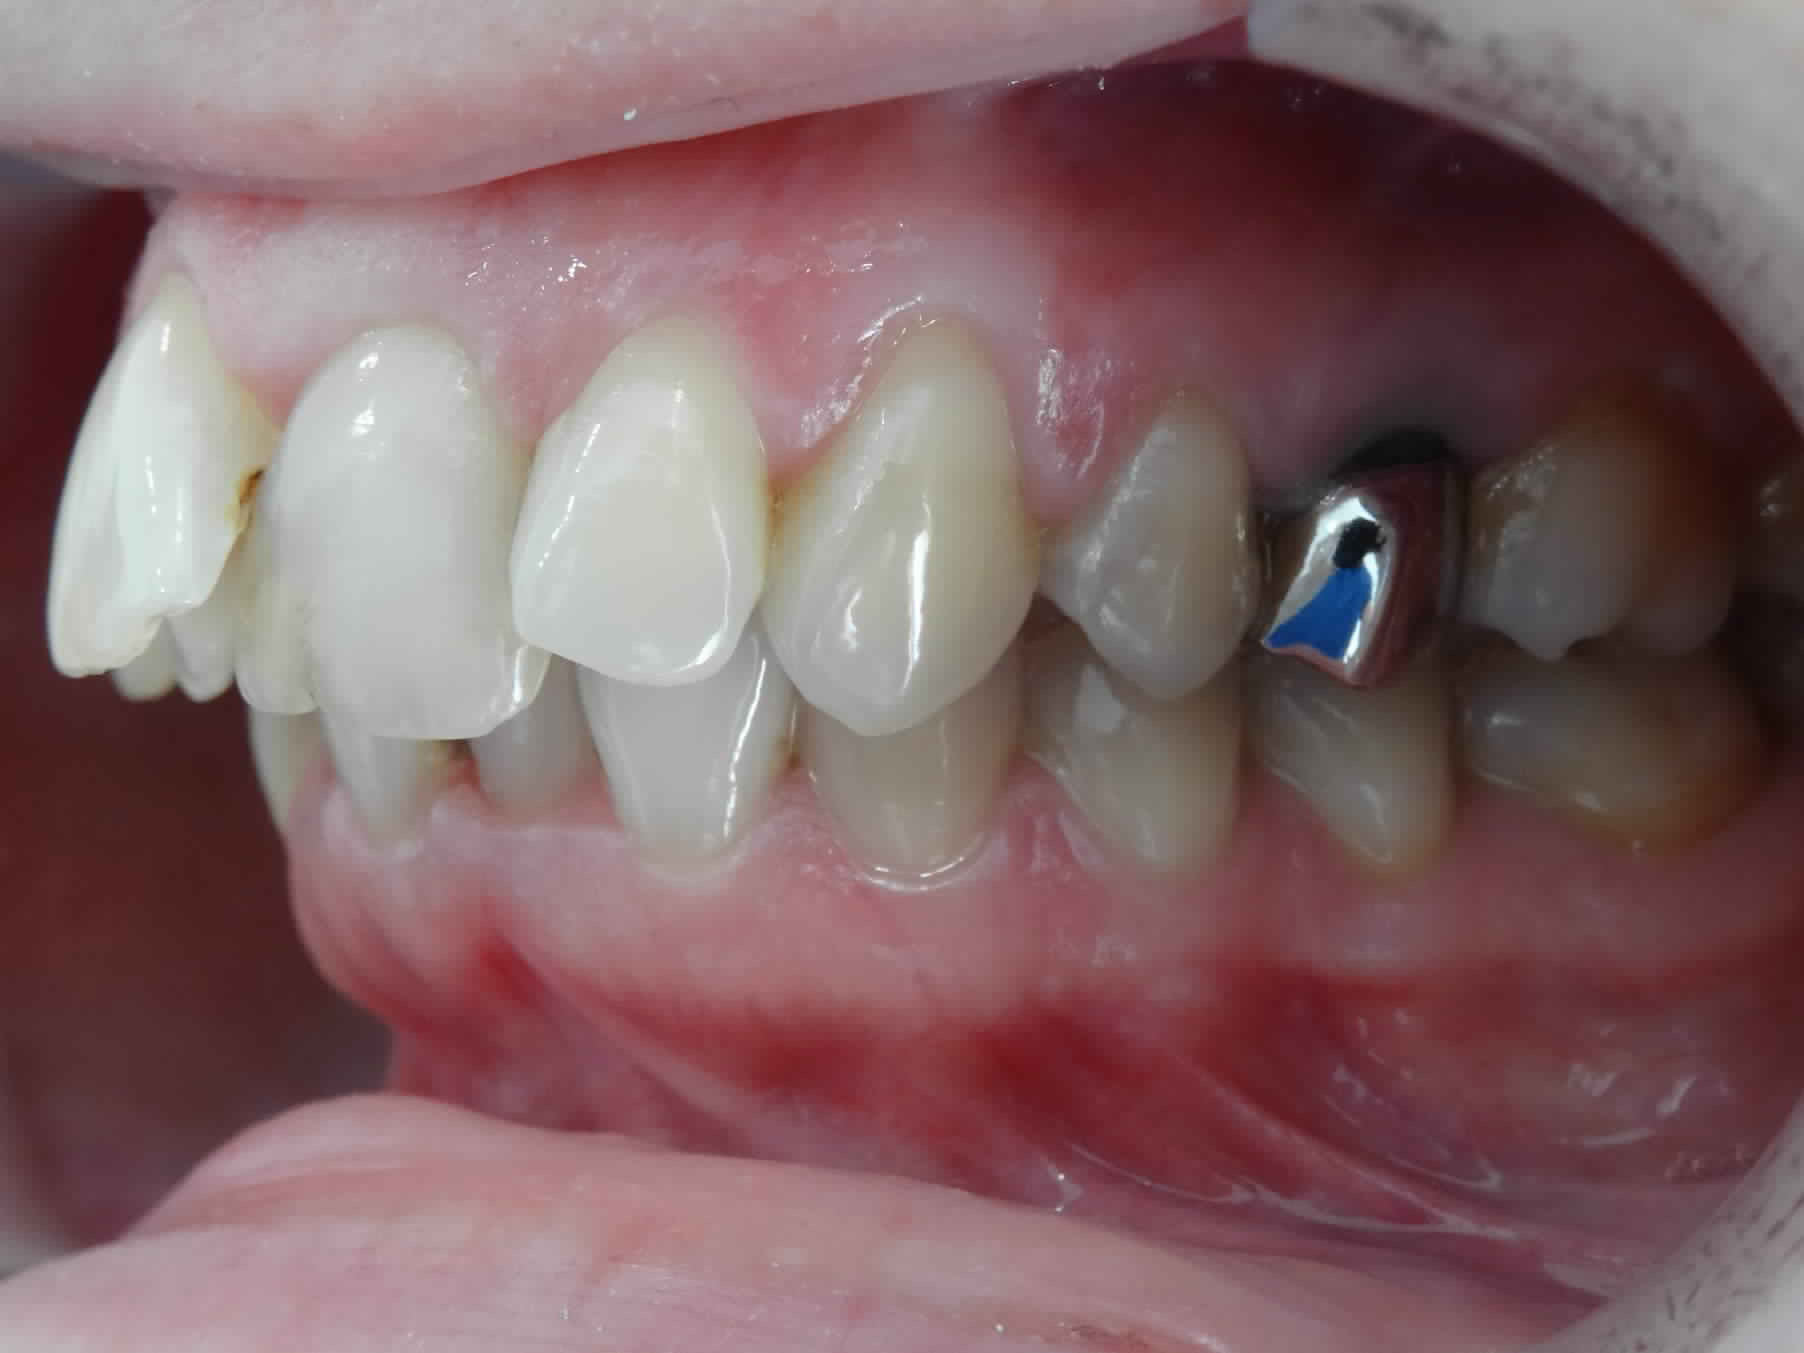

je sollicite vos avis sur ce cas adulte en cours de traitement, avec avulsion des 5 , la supraclusion et la courbe de spee s'est accentuée au cours de la fermeture des espaces , je suis en autoligaturant AO avec des fils actuellement en 14.25 Cuniti ?

1 Il suffit de regarder l’angle que font la prémolaire et la canine par rapport au plan général d’occlusion (surtout la canine sur la vue clinique).

Observe la position de leurs braquets, induite par la distoversion des dents liée au recul (j’écris « braquet » parce que c’est un mot français que les anglo-saxons qui nous l’ont piqué pour nous le retourner perfidement avec une orthographe frelatée).

Tu constates que ce sont ces braquets et eux seuls qui orientent le fil en direction occlusale du côté mésial, ce qui entraine l’égression des incisives.

Regarde l'orientation de ton fil (fig. odf8-1). Ce qui coince, c'est bien le braquet des canines et des prémolaires !